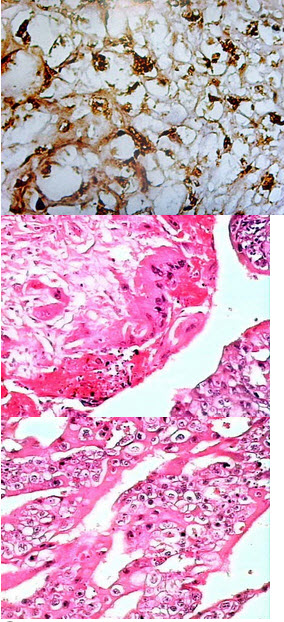

5、单项选择题

女性,41岁,宫颈管内见一赘生物,无色,表面有溃疡,摘除送检,显微镜下见肿瘤细胞呈梭形、上皮样,核大,核仁明显,胞质内有黑色素颗粒(如图)。免疫组化示S-100(+)、HMB45(++)。最有可能的诊断为()

A.恶性黑色素瘤

B.鳞状细胞癌

C.癌肉瘤

D.肉瘤

E.尖锐湿疣